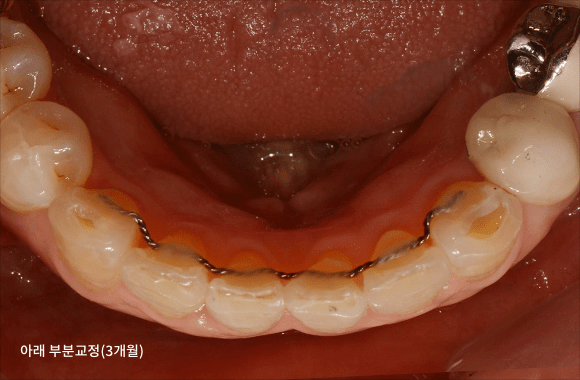

시니어 부분교정